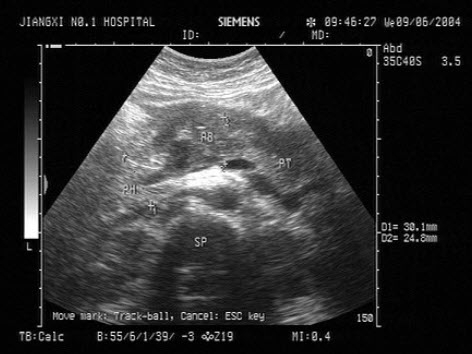

96、单项选择题

如图,最可能的诊断是()

A.软骨成长不全

B.致死性骨发育不全

C.窒息性胸廓发育不良

D.肢体屈曲综合征

E.无肢畸形

97、单项选择题